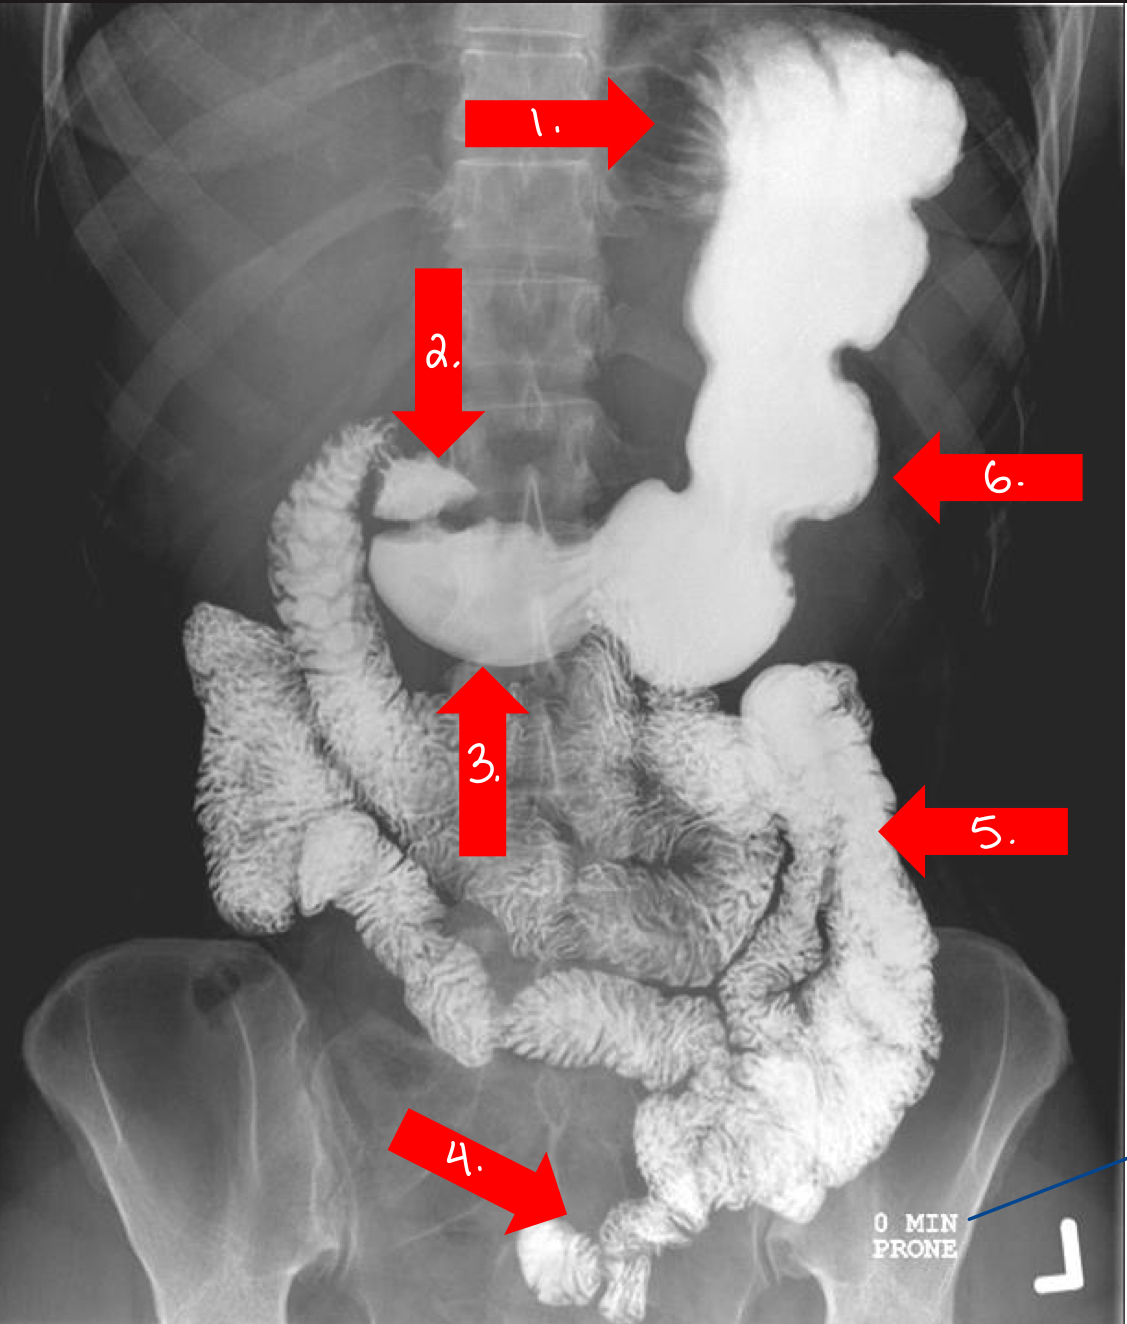

What is 1

gastroesophageal opening

lower esophageal sphincter

sometimes called cardiac antrum/sphincter

What is 2

lesser curvature/stomach

What is 3

doudenal bulb/small intestine

What is 4

jejunum/small intestine

What is 5

pylorus

or pyloric antrum

What is 6

greater curvature/stomach

What is 7

fundus/stomach